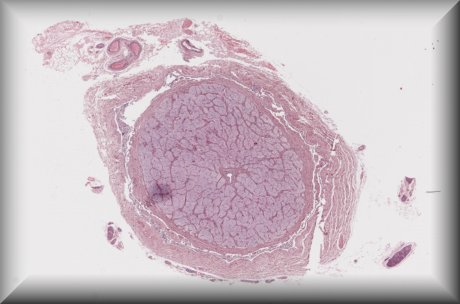

Alexandre Moulin (Laussane): Pigmented ciliary body mass in a 35 yo male. |